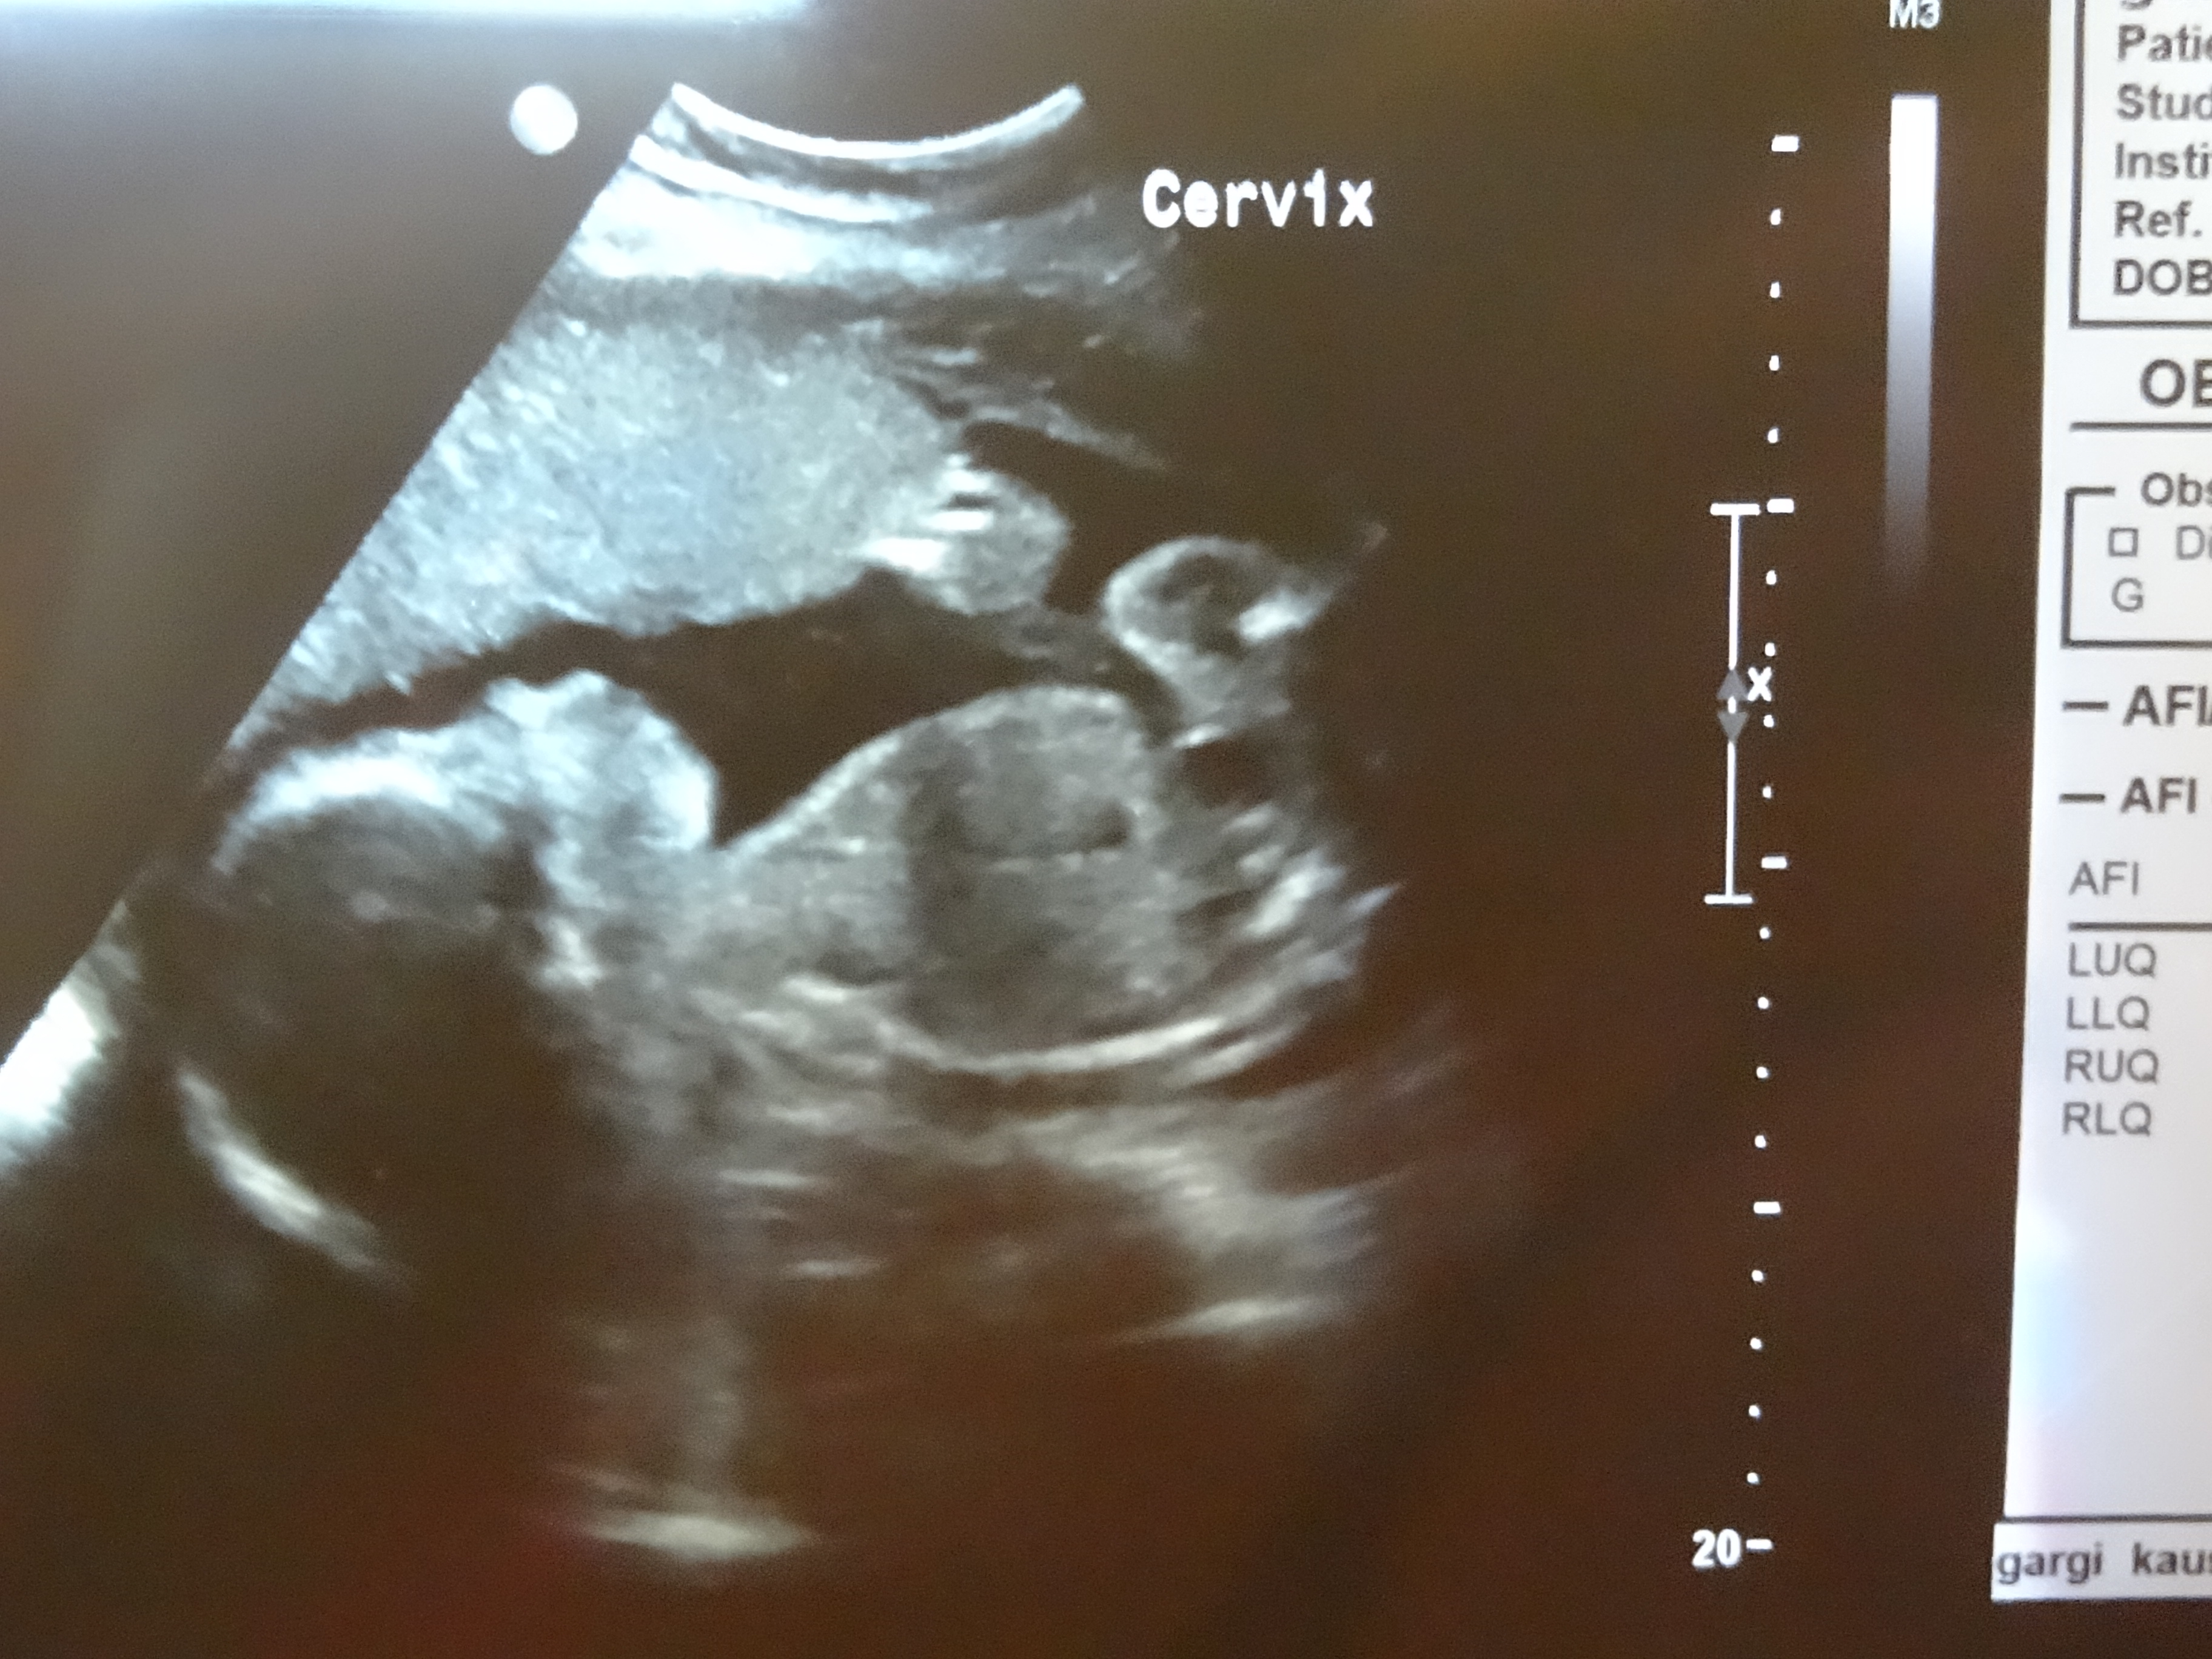

i am a total new to these forums, just trying a shot at it. Here is another one, of thighs & legs,,,, if that can help any guessesAttachment 21189

Please do let me know what makes you think if the pic is blue or pink :-p